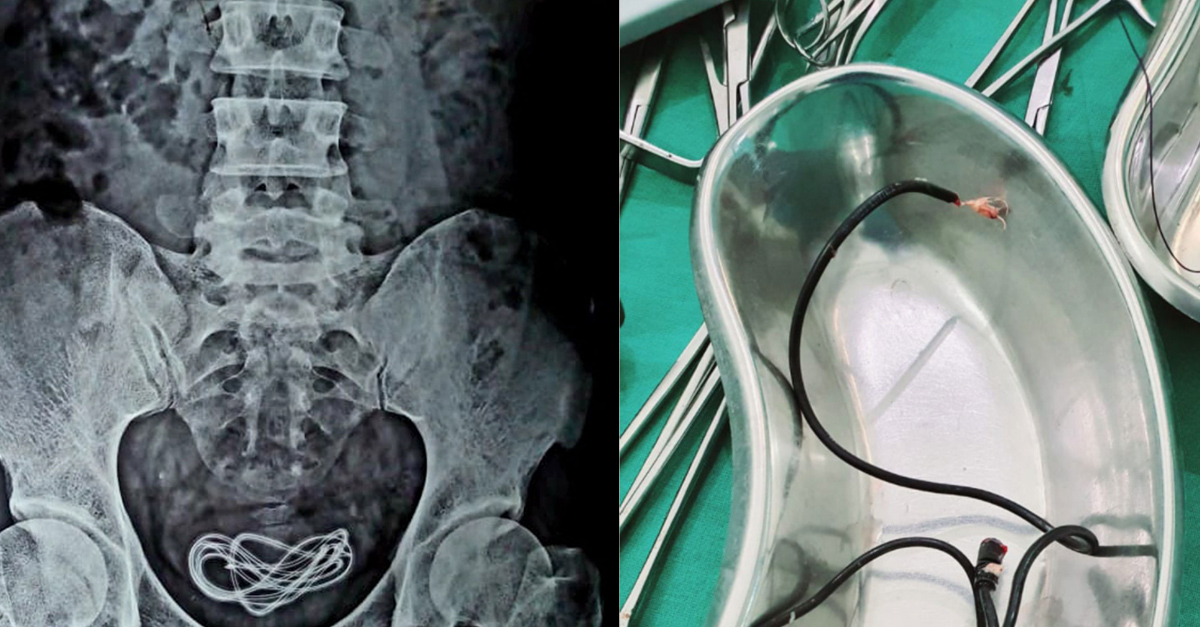

The doctors then made the decision to x-ray. That’s when they found the headphones and decided to perform surgery. When all was said and done they had pulled out a two-foot-long phone charger.

Dr. Walliul Islam said he’d heard of people inserting things into their penises for sexual pleasure — called ‘sounding’ or a ‘catheter fetish’ — and believed that was the case here.